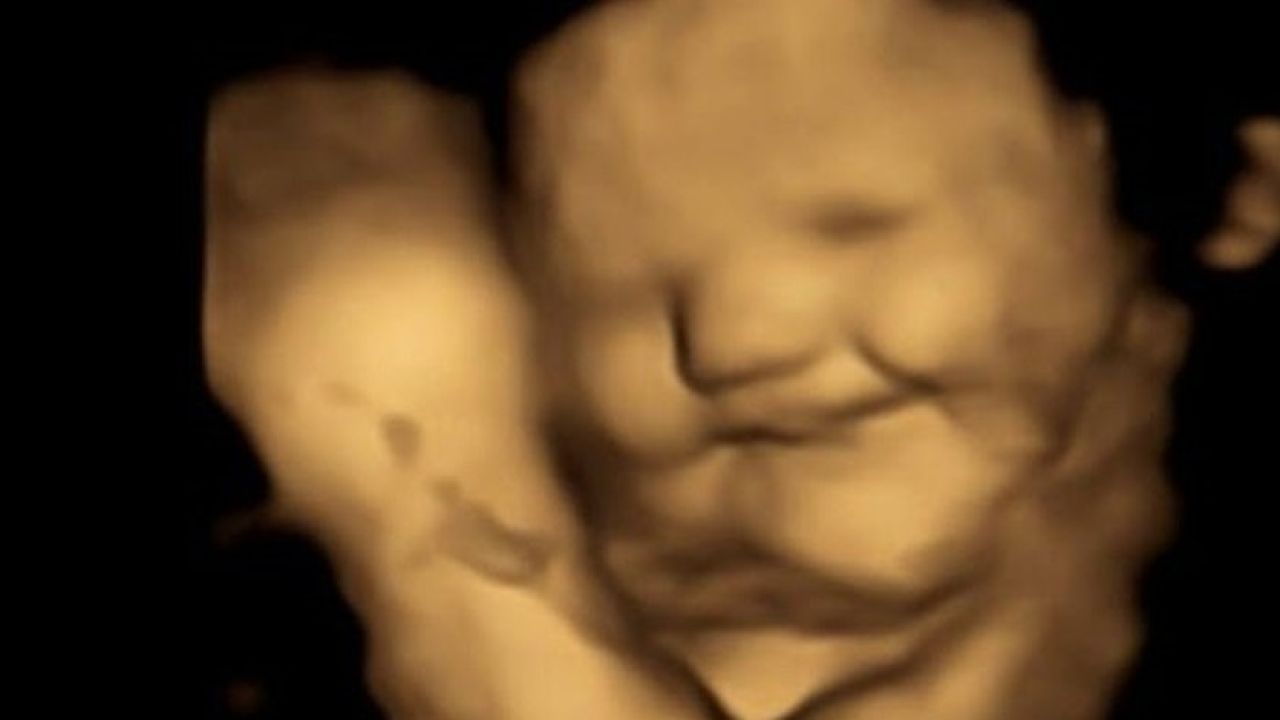

ARAŞTIRMA EKİBİNİN BAŞINDA BİR TÜRK VARKadınlar havuç yediğinde fetüsler gülümserken, laha kapsülü fetüslerin yüzlerini buruşturmalarına yol açtı. Araştırmayı yapan ekibin başındaki isim Beyza Üstün'dü. Üstün, Henüz doğmamış bebeklerin lahana ve havuç tatlarına verdiği tepkileri görmek ve bunları ebeveynleriyle paylaşmak inanılmazdı dedi.

Üstün ayrıca, Bulgular, hamile kadınların yediklerinin doğumdan sonra bebeklerinin tat tercihlerini etkileyebileceğini gösteriyor. Sonuç olarak, doğumdan önce bu tekrarlanan tatlara maruz kalmanın, doğum sonrası gıda tercihlerinin belirlenmesine yardımcı olabileceğini düşünüyoruz. Bu, sağlıklı beslenme ve bebeği sütten keserken yaşanacak 'gıda karmaşasından' kaçınma potansiyeli hakkında fikir geliştirmek için önemli olabilir dedi.